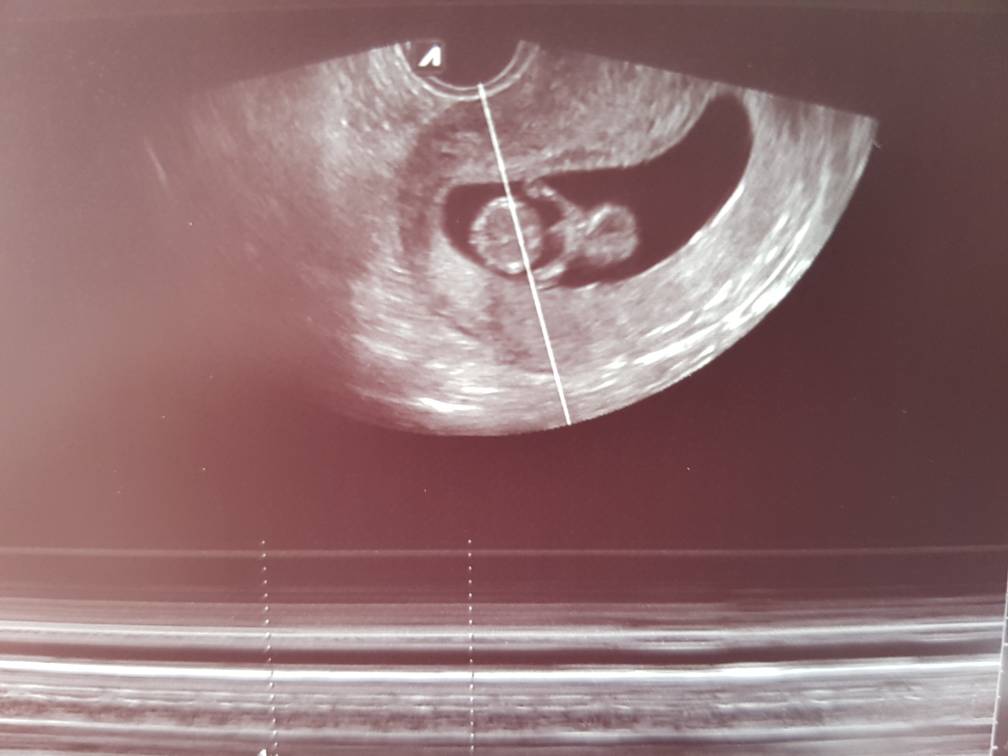

Piekny [emoji173]Jestem już po wizycie [emoji4]

Groszek ma 4.5cm, serce bije jak dzwon, puls 168[emoji173] i bardzo prawdopodobne, że będzie Mateusz [emoji4]

Zobacz załącznik 871165Zobacz załącznik 871166